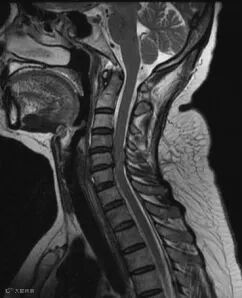

X线和CT显示骨质方面有优势,而MRI可显示:椎间盘、脊髓和韧带病变。对临床形态学变化和功能学评价诊断启关键作用:如椎间盘突出、附件病变、椎管狭窄、脊髓变性、脑脊液循环障碍。

该检者办理入住式体检后,医生根据他的实际情况、制定个性化体检套餐。体检第一天,健康管家一对一陪检、完成已预约好的体检项目。早餐结束后,继续余项检查(麻醉评估通过方可行无痛胃肠镜检查)等,中途可回客房休息。当天晚上在健康管家指导清肠准备。第二天上午在健康管家的陪同下,完成无痛胃肠镜检查。其核磁检查会诊报告单提示:C4-7椎间盘向后突出,压迫硬膜囊,椎体不同程度骨质增生。影像结果:C4-7椎间盘突出;颈椎退行性改变;请结合临床,随诊复查。